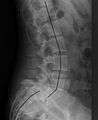

X-ray picture of a grade 1 isthmic spondylolisthesis at L4-5